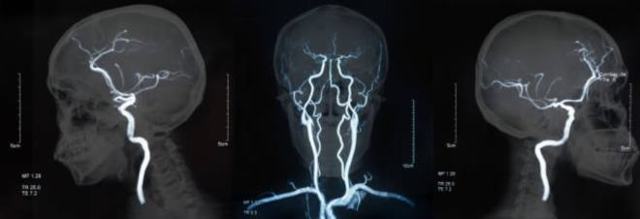

Диагностика аневризмы также включает ангиографию – рентгенологический метод, который проводится в комплексе с применением контрастных веществ.

Благодаря проведению этого исследования можно определить степень сужения того или иного сосуда, выявить расширение сосудов головного мозга, локализацию его разрушения.

Также в спектр диагностических возможностей ангиографии входит выявления слабых мест, то есть аневризм сосудов.

Полученные снимки обследований позволяют оценить состояние кровеносных сосудов и анатомических структур головного мозга в двух проекциях.

Проведение магнитно-резонансной томографии дает специалисту возможность оценить состояние сосудов и головного мозга в послойных срезах.

Благодаря мощному воздействию радиоволн и магнитного поля на послойных срезах четко визуализируются все структуры черепной коробки.

Трехмерное сечение состояния кровеносных сосудов и анатомических образований черепной коробки позволяет поставить точный диагноз.

- ангиография – рентген с контрастом, позволяет увидеть на снимке головной мозг полностью, и тем самым рассмотреть, где локализуется образование;

- КТ-ангиография – совмещение двух вышеуказанных методов;

- МРТ головного мозга – показывает более точную картину сосудов;

Аневризма сосудов головного мозга при проведении КТ-ангиографии

Выявить аневризмы можно при помощи ангиографии с контрастированием, КТ, МРТ (с ангиопрограммой или без нее), транскраниальной УЗДГ.

При подозрении на разрыв аневризмы контрастное вещество при предварительном обследовании не используют, ангиография проводится непосредственно перед началом операции.